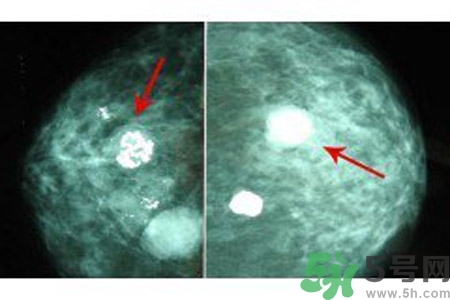

良性惡性乳腺增生鈣化的差異

與良性乳腺增生鈣化相比,惡性乳腺增生鈣化群平均密度較低,密度及大小對(duì)乳腺疾病良惡性鑒別價(jià)值較大。乳腺X線片中微小鈣化分布似乎無(wú)規(guī)律可循,但病理發(fā)現(xiàn)癌腫發(fā)生于末梢導(dǎo)管時(shí),鈣化可位于大片壞死組織中或癌細(xì)胞間,亦可存在于所屬上級(jí)導(dǎo)管內(nèi)或?qū)Ч芊植嫣幓蛳噜徬倥萸粌?nèi)。